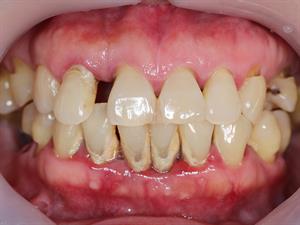

3. புறத்திசு நோய்

நோய் காரணி: இவ்வகை நோய் புகையிலையை மெல்லுவதால் ஏற்படுகிறது.

தாக்கங்கள் /விளைவுகள்: புறத்திசு நோயினால் ஈறுகள் முழுமையாக நோயின் முற்றிய நிலையை அடைந்து எலும்புகள், ஈறுகள் மற்றும் பிறதிசுக்களை அழிக்கிறது.

தீர்வுகள்:

- புகையிலை மெல்லுவதைத் தவிர்க்க வேண்டும்.

- சரிவிகித உணவு முறையைப் பின்பற்ற வேண்டும்.

புறத்திசு நோய்